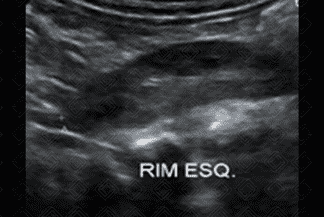

Texto alternativo para a imagem Figuras 1, 2, 3 e 4. Créditos: Dra. Elazir Mota - Rio de Janeiro/RJ

Descrição das figuras 1, 2, 3 e 4: Ultrassonografia das vias urinárias evidenciando rins em ferradura. Observe que o rim esquerdo é menor e apresenta alteração rotacional. Ao avaliar a linha média, anteriormente à aorta, observa-se a fusão dos polos renais inferiores.

• Ultrassonografia das vias urinárias: N ota-se fusão dos pólos inferiores dos rins na linha média, anteriormente à aorta (como nas imagens radiológicas). Sempre avaliar bexiga e sistema coletor, buscando por sinais de dilatação, já que nestes casos é comum a dificuldade de drenagem nas pelves renais;